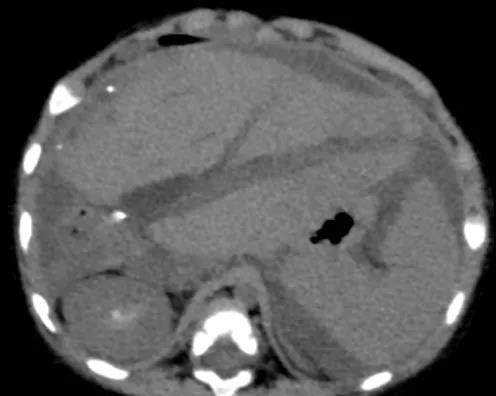

术后第8天,发热加重,白细胞、CRP、PCT进行性升高,患儿引流管每日引出脓性液体10-20mL,彩超提示腹腔内无明显包裹性积液,见图1。

▲图1 腹部CT